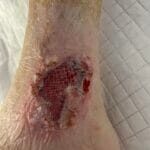

Enrolled Nurse (EN): Permitted Procedures

This page provides a quick reference of Care Plans and Tutorials available on The Wound Sandwich (TWS) which are permitted to be undertaken by staff with a Enrolled Nurse (EN) qualification. Additional applicable qualifications are also listed.